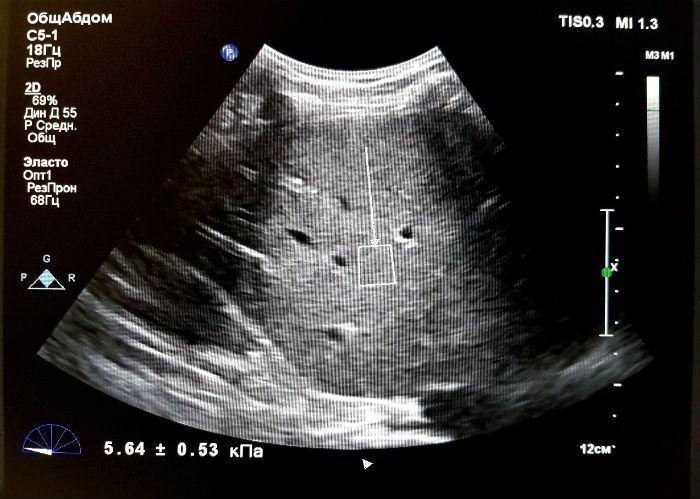

Исследование печени

При развитии такого патологического состояния, как фиброз или цирроз печени, решающую роль обычно играла пункционная биопсия. В ходе этой манипуляции чрескожным доступом с помощью тонкой иглы осуществлялся забор ткани печени, которая затем подвергалась микроскопическому исследованию. Но данный способ является дорогостоящим и может сопровождаться побочными эффектами. Кроме того, для получения морфологического результата требуется время.

Эластосонография предоставляет врачу гораздо больше потенциальных возможностей для получения достоверной информации о состоянии пораженного органа, в данном случае - печени. Причем процесс не отнимает много времени, ведь сама процедура занимает не более 15-20 минут, а результат готов сразу же после обследования. Достоверность этого метода варьируется в диапазоне 87-99%, что выводит эластрографию в разряд наиболее достоверных и чувствительных диагностических методов.

Показания к проведению эластографии печени:

1. определение наличия фиброзного изменения печеночной ткани;

2. определение стадии фиброза печени;

3. проведение дифференциального диагноза между гемангиомой и злокачественным поражением печени;

4. оценка состояния внутрибрюшных лимфатических узлов.

Так выглядит на эластографии здоровая печеньТак выглядит на эластографии здоровая печень